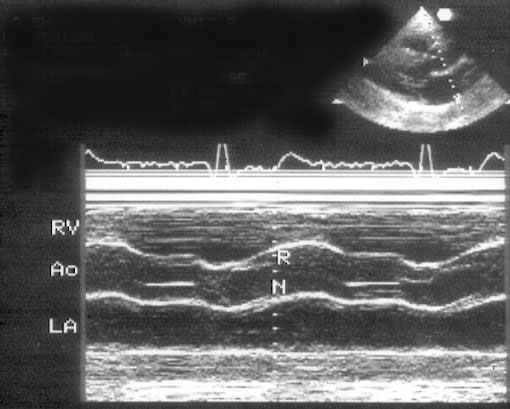

Обязательная часть эхокардиографического исследования — это М-модальное исследование, которое почти всегда проводится исключительно из позиции парастернальной длинной оси левого желудочка. На рис. 2.2, 2.3, 2.4 приведены изображения стандартных позиций М-модального исследования. Двумерное изображение помогает правильно ориентировать ультразвуковой луч для М-модального исследования.

Рисунок 2.2. М-модальное исследование аортального клапана и левого предсердия. Левая коронарная створка аортального клапана не видна, а правая коронарная и некоронарная створки в систолу образуют «коробочку». Для правильного измерения переднезаднего размера левого предсердия ультразвуковой луч должен проходить перпендикулярно его задней стенке. RV — правый желудочек, Ao — аортальный клапан и корень аорты, LA — левое предсердие, R — правая коронарная створка аортального клапана, N — некоронарная створка аортального клапана.